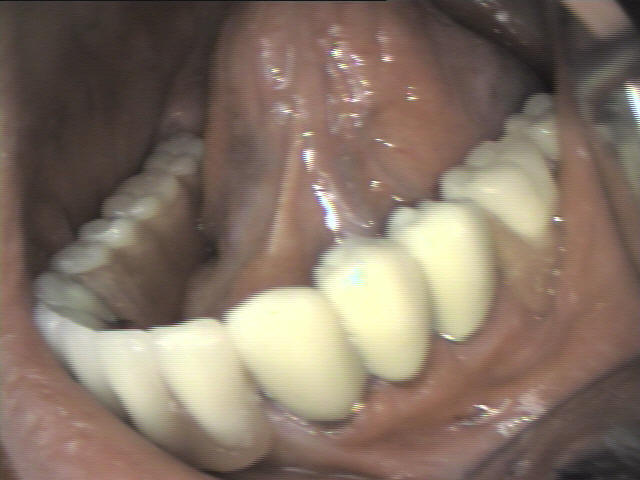

Teleskopprothese

(Deckprothese) mit 5 Teleskopkronen im Unterkiefer

Ein herausnehmbarer Zahnersatz auf 5 eigenen Zähnen. Die ersten Kronen (Primärkronen) sowie die zweiten Kronen (Sekundärkronen) wurden aus Edelstahl (kostengünstig) angefertigt.

Zwischen den Teleskopkronen spezieller Kunststoff eingebracht, um Friktion der Prothese und Passgenauigkeit der Kronen, zu erreichen. Er muss ab und zu, ja nach der Abnutzung, ausgetauscht werden.